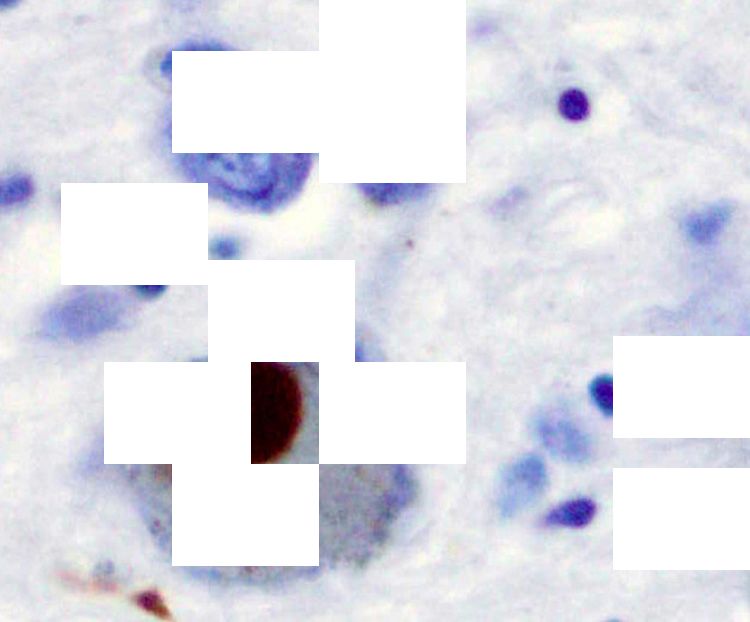

A brown stain indicating the presence of alpha-synuclein in a Lewy body, obscured by white blocks to represent missing information about the protein

A brown stain indicating the presence of alpha-synuclein in a Lewy body

Alpha-synuclein stained brown in a Lewy body in the substantia nigra. Credit: Wikimedia images / Marvin 101.

Scientists then attempted to raise antibodies against this so-called problem protein. They examined brain tissue and found alpha-synuclein in Lewy bodies – complex, round inclusions in cells that are the characteristic pathological features of Parkinson's.

However, they also discovered that the protein had spread throughout the brain in end-stage Parkinson’s. Clearly, dopamine cells were just one part of the story.